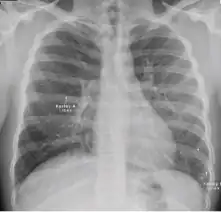

Chest X-ray of a person with advanced tuberculosis: Infection in both lungs is marked by white arrow-heads, and the formation of a cavity is marked by black arrows.